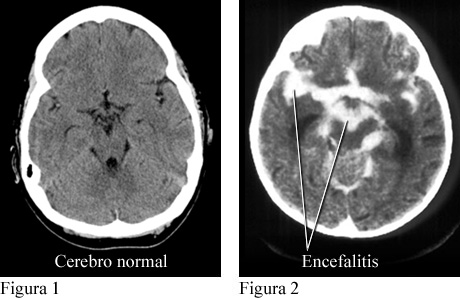

Encefalitis